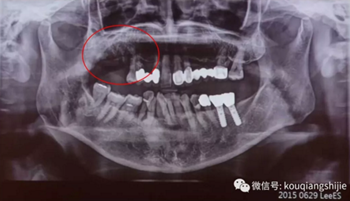

這個患者是在別的醫(yī)院拔牙后1個月來到我們醫(yī)院

我們從CT上可以看到#16,17的拔牙創(chuàng)破壞非常嚴重

但是因為是剛拔牙1個月,所以我覺得這個拔牙創(chuàng)應(yīng)該可以愈合

我們再多等了3個月

3個月后我們發(fā)現(xiàn)缺損部位的黏膜愈合的非常不規(guī)則

翻瓣后發(fā)現(xiàn)也沒有完全形成骨質(zhì)。